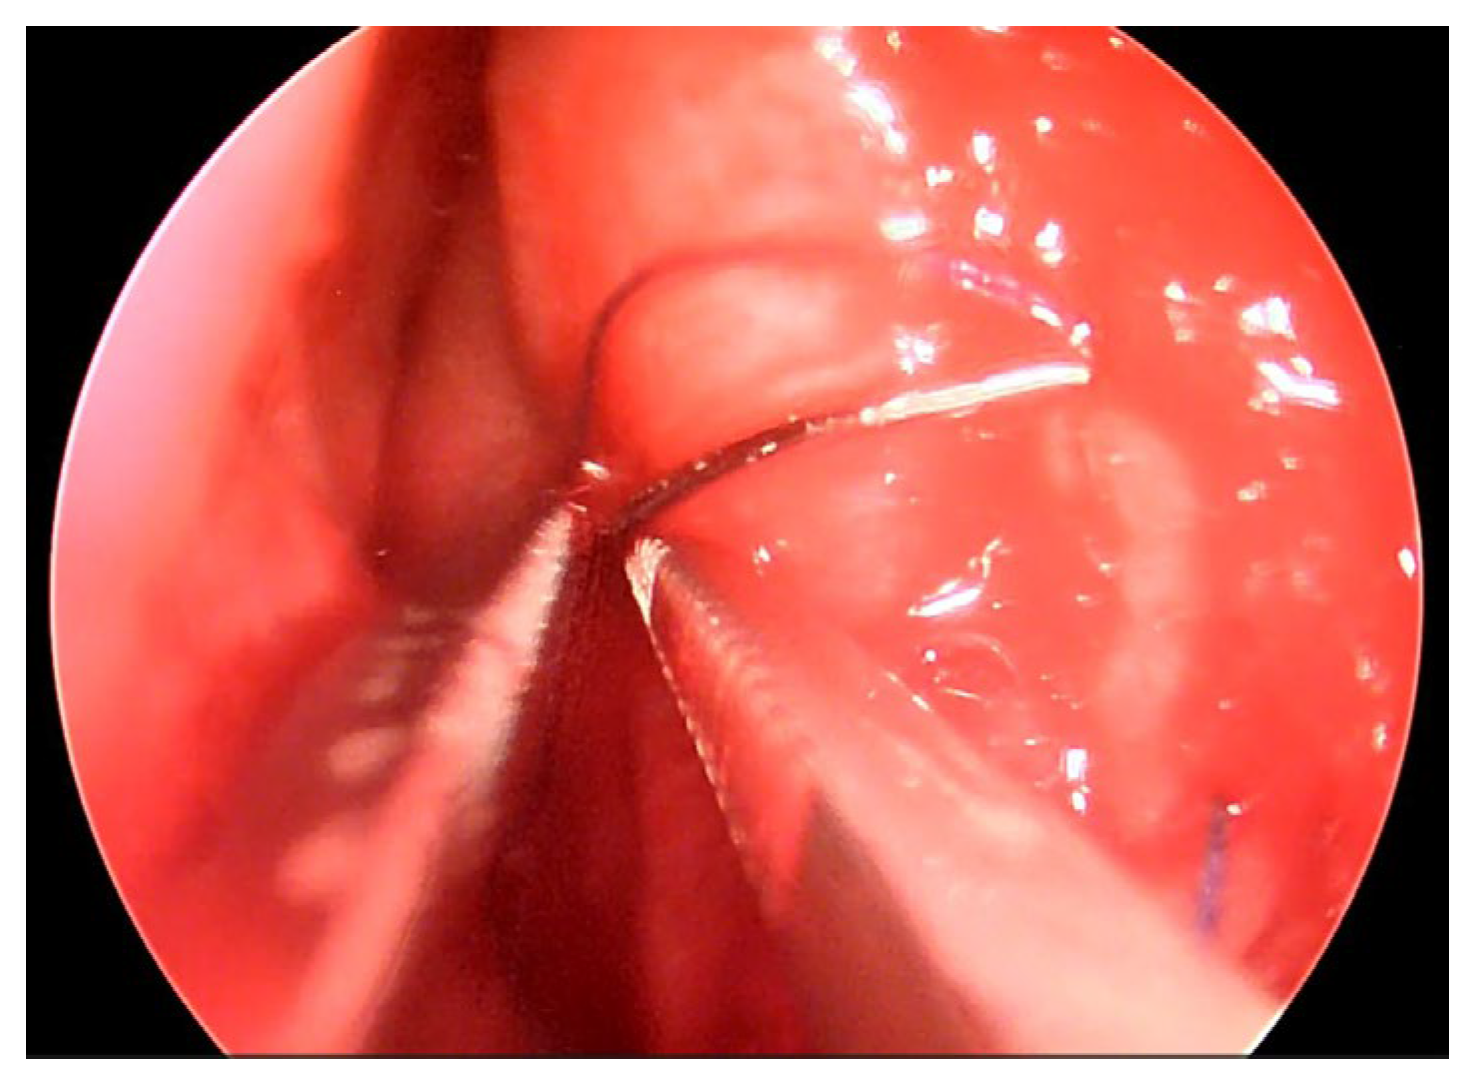

The patient underwent an Endoscopic One Nostril Transseptal Transsphenoidal Approach (EONOTTA) for tumor removal. In Figure 2 is shown the right mono-nostril approach and the septal mucosal incision with the initial submucosal dissection along the septum.

Figure 2. Mono nostril approach and septal mucosal incision.